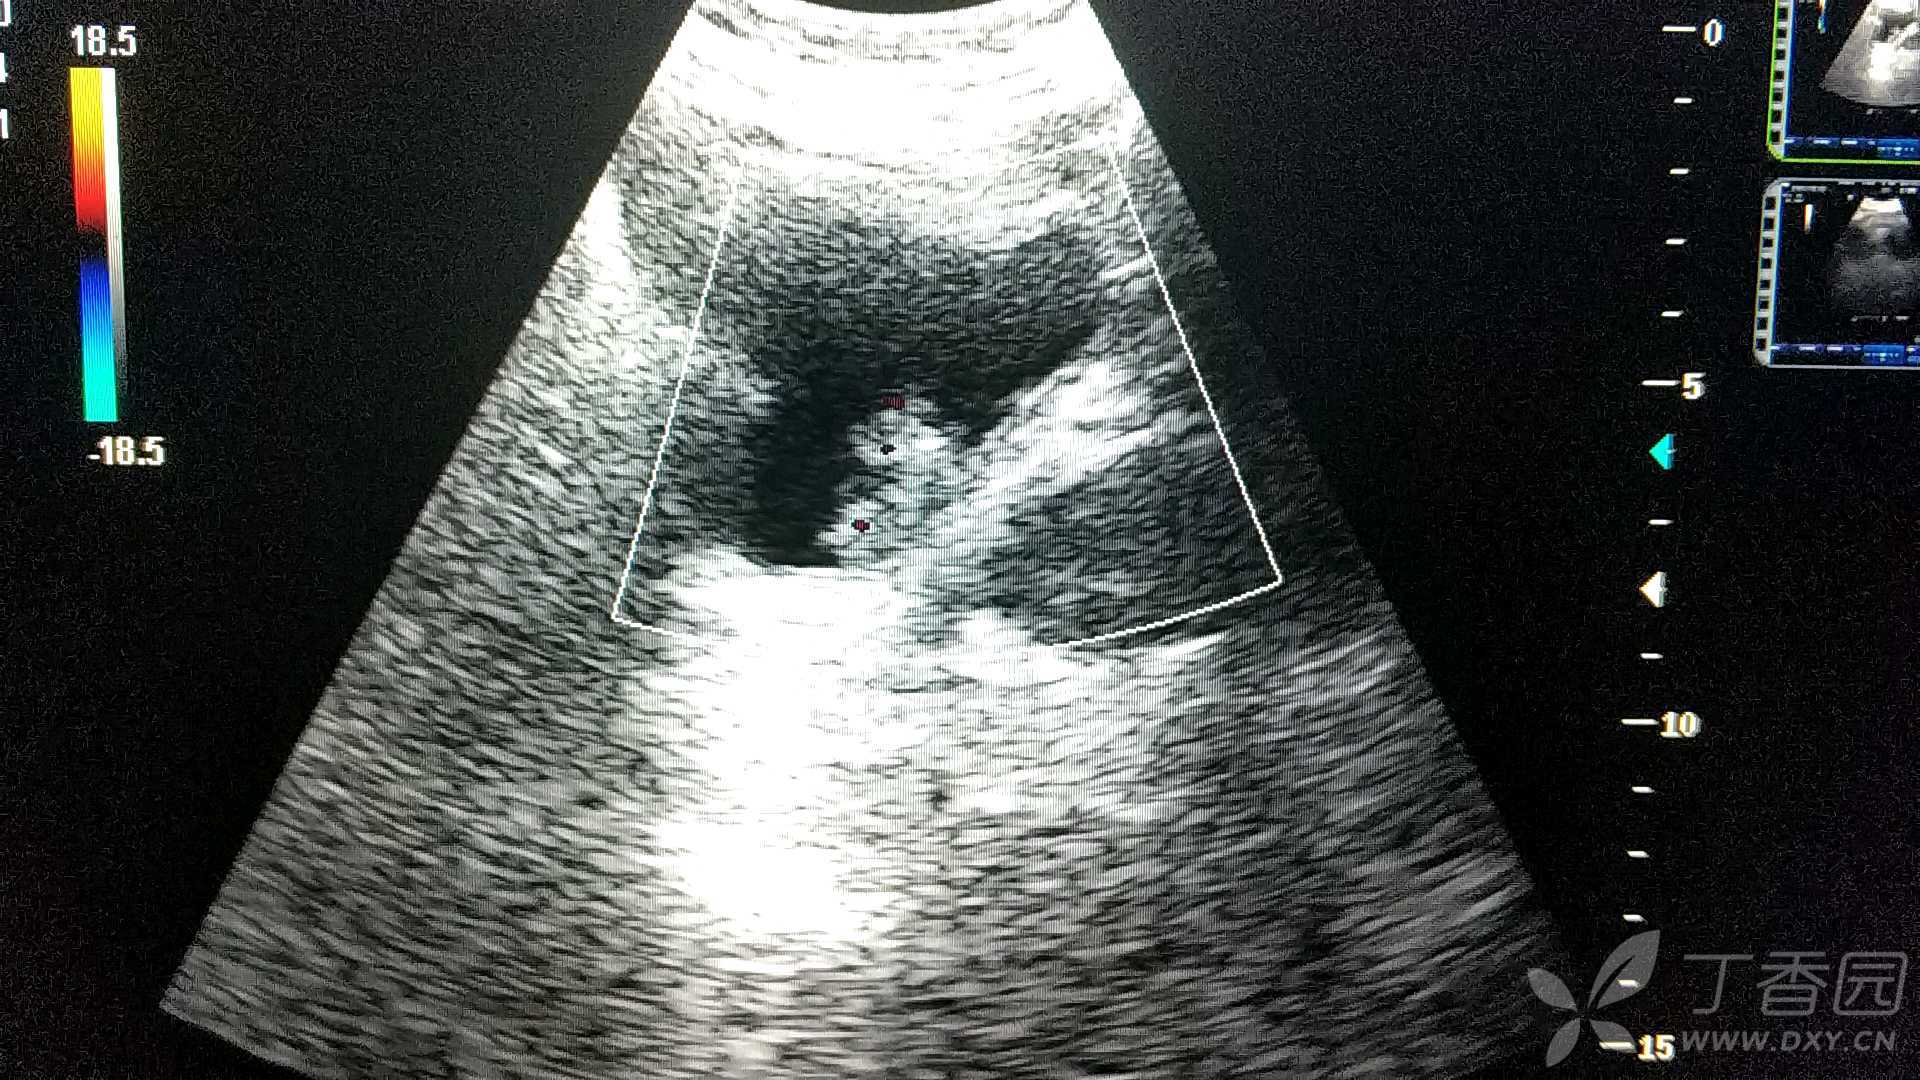

超声入门贴41-----膀胱癌

图片尺寸768x576